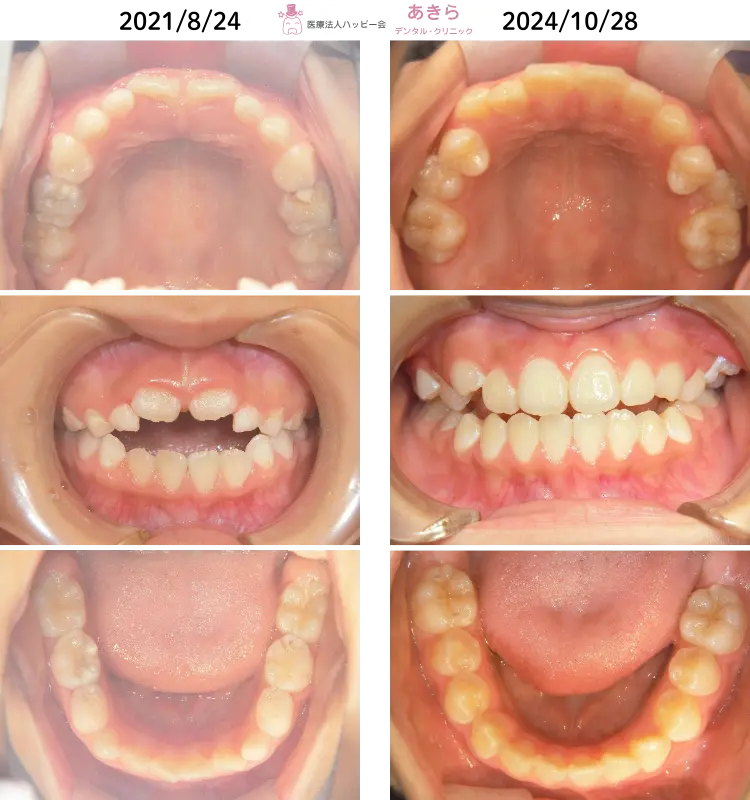

舌前突癖を伴うケース

8歳7ヶ月 ⇒ 11歳9ヶ月

- 上顎左右1番萌出遅延~低位 ⇒ 前歯部開咬

- 上唇小帯付着異常

- 下顎前歯部叢生

- 脱灰著名(ホワイトスポット)

- 乳歯むし歯(++)

- 下顎前突(反対咬合) ⇒ 上顎骨前方成長不足による

- 上顎左右1番捻転

- 正中離開

2021年8月24日 ⇒ 2024年10月28日(2022年1月 プレオルソスタート)

※叢生(凸凹)と反対咬合を伴う開咬症例です。

- 2022年1月

- 上唇小帯切離移動&上顎左右B番抜歯後

- 「プレオルソ X タイプⅡ」スタート

- プレオルソ拡大を随時行っております。

- 2023年9月より

- 「ハビットコレクターユース」へ装置変更

- 日中1~2時間使用と就寝時の使用を厳守していただきました。

2年9ヵ月

12回